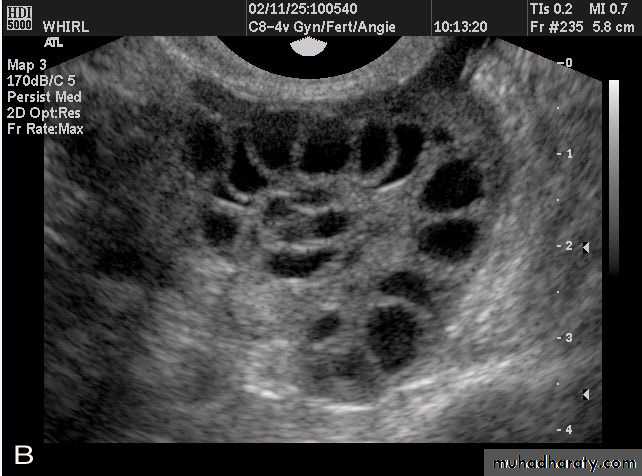

Images from women with differing expressions of the four major subtypes of the metabolic syndrome associated with polycystic ovary syndrome (A–D). The images exhibit quite differing ultrasonographic appearances in the size and distribution of follicles within PCOS ovaries. A recent corpus luteum is clearly visible in the ovary in panel (D).

• POLYCYSTIC OVARY SYNDROME